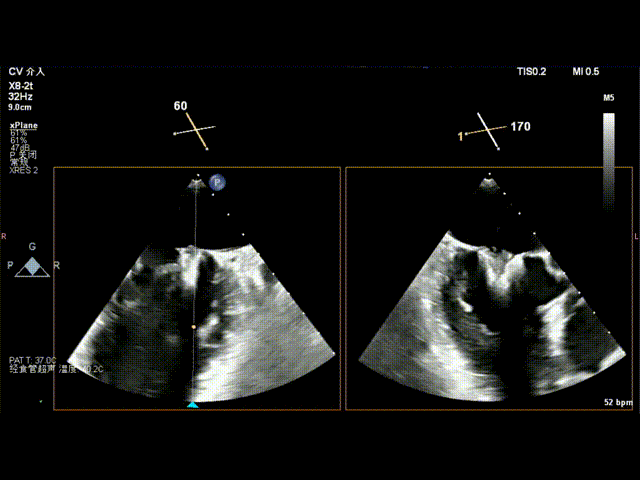

术前食道超声示: 二尖瓣重度反流,1区脱垂并累及外交界。

术前食道超声-2D血流

术前食道超声-3D

术前食道超声3D血流